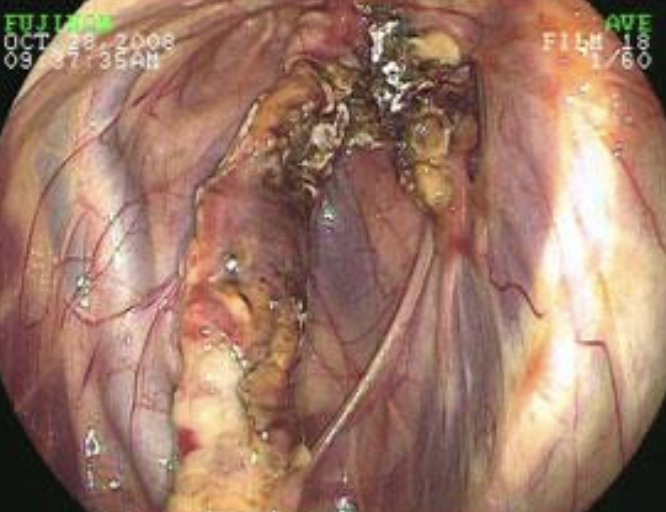

1. endoscopy (visualization of blood in trachea)

2. ultrasound: liver abscess, dilation of CVC